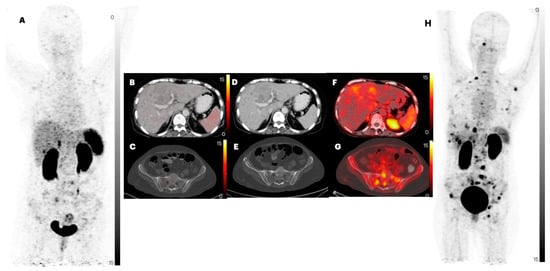

2.1. Biodistribution of [68Ga]Ga-DATA5m-LM4

2.2. Comparison of Lesion Detection and Uptake between [68Ga]Ga-DOTANOC and [68Ga]Ga-DATA5m-LM4

| Organ | SULpeak | SULavg | ||||

| DATA5m -LM4 | DOTANOC | p-Value | DATA5m-LM4 | DOTANOC | p-Value | |

| Liver | 2.5 | 3.5 | 0.01 | 2.0 | 2.7 | 0.015 |

| (1.7 to 3.8) | (2.4 to 5.3) | (1.3 to 3.1) | (1.9 to 4.0) | |||

| Spleen | 6.6 | 11.3 | <0.0001 | 5.7 | 10.3 | <0.0001 |

| (4.0 to 9.7) | (7.2 to 18.3) | (3.7 to 8.6) | (5.8 to 13.9) | |||

| Kidney | 9.8 | 6.1 | 0.0004 | 8.9 | 4.2 | <0.0001 |

| (6.6 to 13.8) | (4.1 to 9.6) | (5.9 to 11.5) | (2.9 to 6.8) | |||